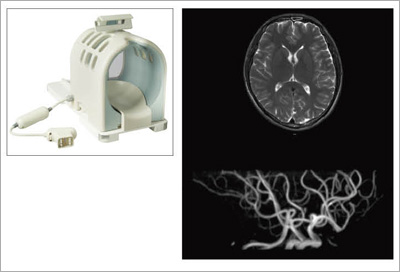

図6に,新たに開発されたOASISのRAPID Headコイルの外観と画像例を,図7に,RAPID Bodyコイルの外観と画像例を示します。それぞれ,ソレノイドコイルベースの高感度マルチコイルシステムで,すべての撮像方向で最大2倍のRAPID計測が行えます。

![]() 図6 RAPID Headコイルと画像例 |